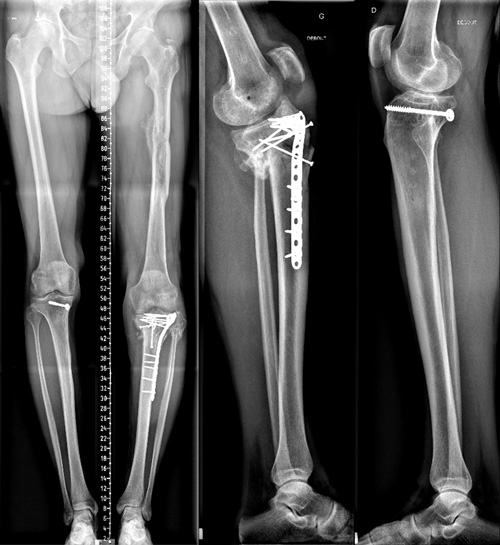

8 Months xrays

Knee stable but stiff walk without crusches

8 Months xrays Knee stable but stiff walk without crusches